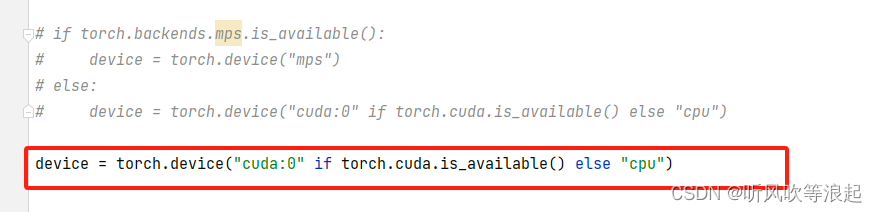

要是出现上述错误,因为toch版本不对,这里直接将代码修改即可。红色框就是修改后的代码,源代码是被注释的四行